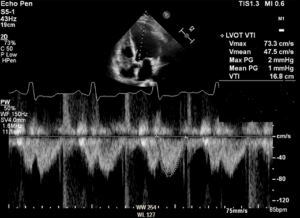

Echo data are shown below. If LVEF is 35% and BSA (body surface area) is 1.8m², findings are consistent with which of the following: